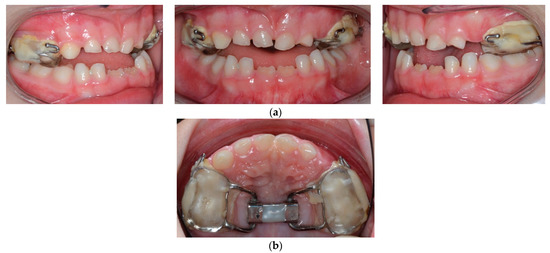

2. Case Report

4. Treatment Progress